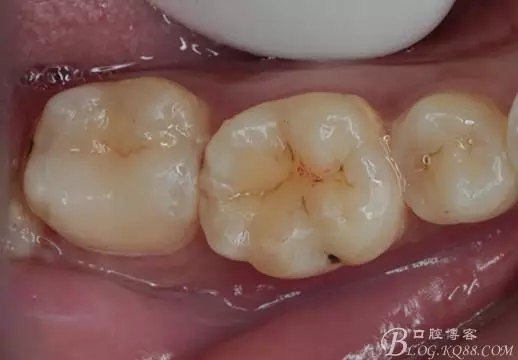

一周后復(fù)診,37臨時(shí)充填物完好。去除臨時(shí)充填物,清潔基牙,試戴嵌體,就位良好,邊緣密合。取下嵌體,常規(guī)處理,9.5%HF處理20S,沖洗一分鐘,95%酒精蕩洗5分鐘?;劳磕?7%的磷酸凝膠,釉質(zhì)區(qū)域酸蝕30S,本質(zhì)區(qū)域15S。粘固用的是3M第八代粘接劑套裝,照說明書逐步操作。最終固化時(shí)涂滿阻氧劑,每個(gè)牙面最少光照30S,光固化燈用漸強(qiáng)模式。常規(guī)調(diào)合,配合硅膠尖套裝拋光。術(shù)后常規(guī)醫(yī)囑,不適隨診。

④嵌體顏色與基牙的差異也是一遺憾。